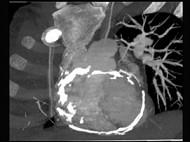

问题 男性45岁,心悸气促乏力,下肢肿胀半年余,曾患肺结核,胸部CT扫描如图所示,请选择正确的选项为 ( )

选项 A、X线、CT为常用检查方法 B、MRI显示增厚的心包较X线、CT优越,但是对心包钙化不敏感 C、心包钙化显著时也可称之为“盔甲心” D、心包钙化多见于结核 E、考虑为缩窄性心包炎 一、多项选择题

答案 ABCDE